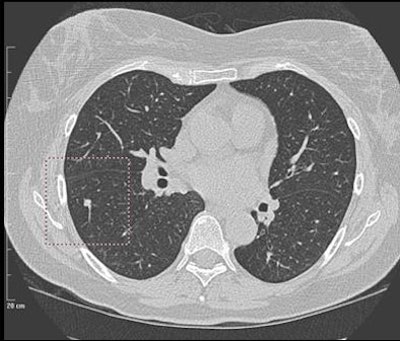

| Solid nodule of 6 mm in right lower lobe was a false negative, found by the radiologist but not marked by CAD. |

Most (13/28) false negatives were pleura-based, and were more prevalent in the right lung (n = 19) than the left lung (n = 9), with an average size of 9 mm.